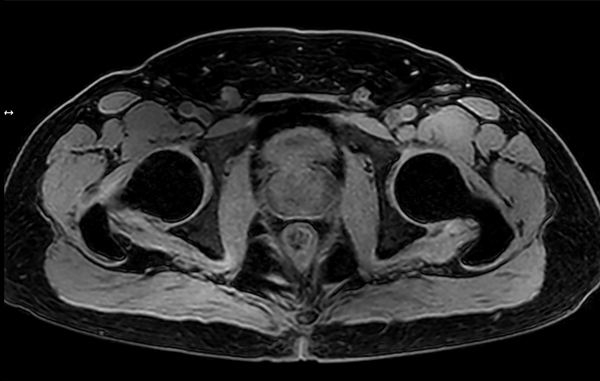

Motion-free Prostate imaging